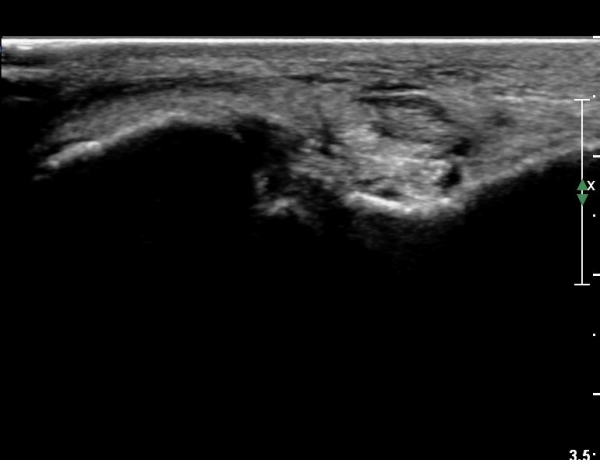

¹ß¸ñ ¾ÕÂÊ Á¾´Ü¸é°Ë»ç¿¡¼­ °üÀý³» ºÎÁ¾À» º¸ÀδÙ(»çÁø 1).

°üÀý³» ºÎÁ¾Àº ½É°¢ÇÑ ¼Õ»óÀ» ¾Ï½ÃÇÏ´Â ¼Ò°ßÀÌ´Ù.